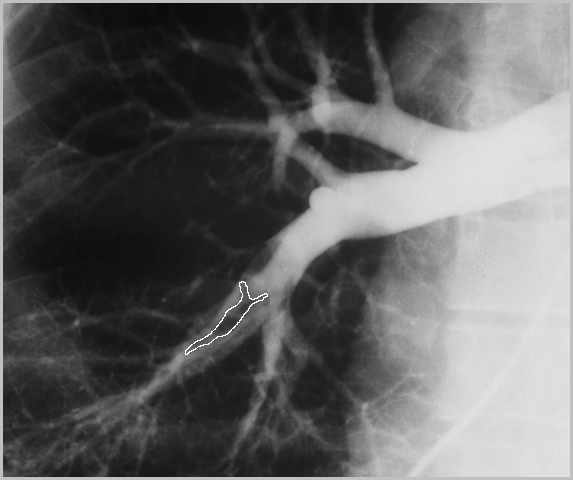

EMBOLIA PULMONAR

ARTERIOGRAFIA PULMONAR

Defectos intraluminales de llenado